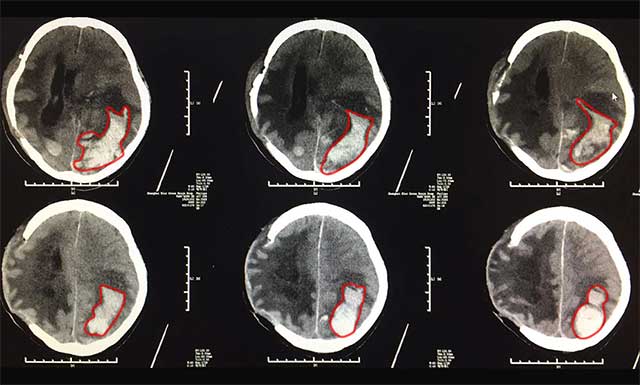

▲標(biāo)記處為出血部位,患者情況危急

2月16日早上,醫(yī)生查房時(shí)發(fā)現(xiàn)患者李家民瞳孔有散大的情況,眼睛對光反應(yīng)也消失了,考慮患者有再出血的可能,建議患者立即通過腦卒中“急診綠色通道”進(jìn)行頭顱CT檢查。醫(yī)院為了縮短腦卒中患者的搶救時(shí)間,特設(shè)立“急診綠色通道”, 為腦梗死、腦出血患者急診救治贏得了寶貴時(shí)間。

影像提示,患者腦出血術(shù)后改變,潘仁龍主任當(dāng)機(jī)立斷,立刻組織了神經(jīng)外科6B病區(qū)吳治群博士進(jìn)行緊急會(huì)診,患者左側(cè)額顳頂枕葉有一個(gè)很大的血腫,根據(jù)患者病史、病癥及影像學(xué)表現(xiàn),考慮患者這次腦出血為淀粉樣腦血管病變或血管畸形破裂所致。并一致認(rèn)為患者手術(shù)指征明顯,腦出血情況緊急,出血量也比較多,已經(jīng)危及生命,必須立即手術(shù),才能挽救患者生命。